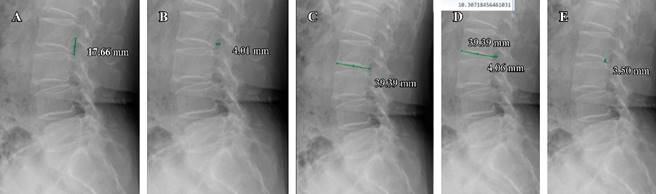

All measurements were conducted by a resident physician in traumatology and orthopedics, who assessed the foramina from L1-S1, and performed the following measurements: 1) Foraminal height, measuring the distance between the pedicles; 2) Foraminal width, extending from the posterior edge of the vertebral body to the anterior edge of the superior articular process. In cases where there were two posterior edges due to obliquity or rotation of the vertebral body, the most posterior edge of the vertebral body was taken as a reference. 3) Lower endplate, measured from its anterior limit to its posterior edge; 4) Posterior disc height, measured as the distance between the posterior edges of the vertebral endplates. These measurements are illustrated in Figures 1 and 2.

Figure 1: Lateral radiograph of the lumbar spine in a weight-bearing position. A) Measurement of foraminal height. B) Measurement of foraminal width. C) Measurement of the inferior endplate. D) Index of foraminal width/inferior endplate platform with a result of 10%. E) Measurement of posterior disc height.

Following the measurements, the foraminal width/lower endplate (FW/LE) index was calculated. This index is obtained by dividing the measured foraminal width by the lower endplate measurement and multiplying the result by 100 to express it as a percentage.

During this study, a consensus was reached among 3 spine surgeons in the service, establishing that a foraminal width/lower endplate index of less than 10% suggests performing direct decompression. This decision is based on the inference that with a bone distance of less than 4 mm in foraminal width, there will be compression and morphological changes of the nerve, despite the removal of soft structures such as intervertebral disc or ligamentum flavum. This inference is supported by the understanding that the nerve root occupies approximately between 23.89 and 32.18% of the foraminal area depending on the lumbar level.11,13